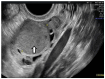

Endometriosis is a multifaceted gynecological disorder defined by endometrium-like tissue outside the uterine cavity. It is mainly localized in the pelvis and creates a local inflammatory environment responsible for its manifestations and complications. In 30-50% of cases, endometriosis is associated with infertility. In 17-44% of cases, the ovaries are affected in the form of ovarian endometriomas (OEs). The symptoms of OEs are not very pronounced. The development is slow. Diagnosis is difficult because OEs resemble cystic ovarian pathology, which is so diverse. The actual diagnosis is possible through direct visualization or laparoscopy. Surgical treatment by cystectomy is common for OEs. Recently, other therapeutic modalities have emerged that have less impact on ovarian reserves and pregnancy rates. In this context, the review attempts to shed light on the best diagnostic and treatment methods for an insidious pathology with a major impact on fertility.